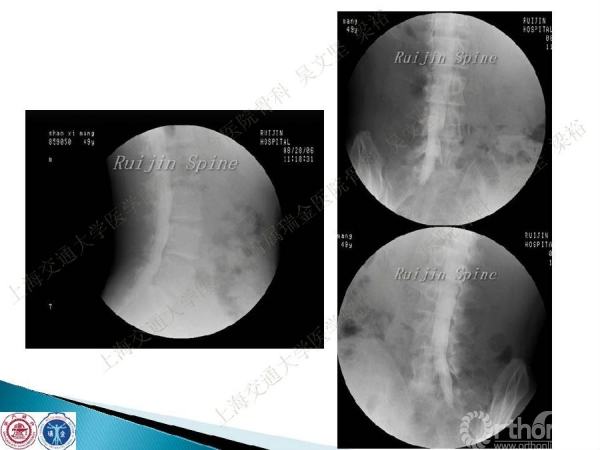

腰椎融合术后临近节段发生的退行性病变(adjacent segment disease,ASD))是一种常见的并发症。ASD的发病率相当高,而且涉及的范围很广。传统翻修手术治疗ASD有软组织剥离多、出血多、术后康复时间较长以及引起新的并发症的风险。本文结合病例介绍了运用Stand alone DLIF技术治疗ASD的方法与其优势。